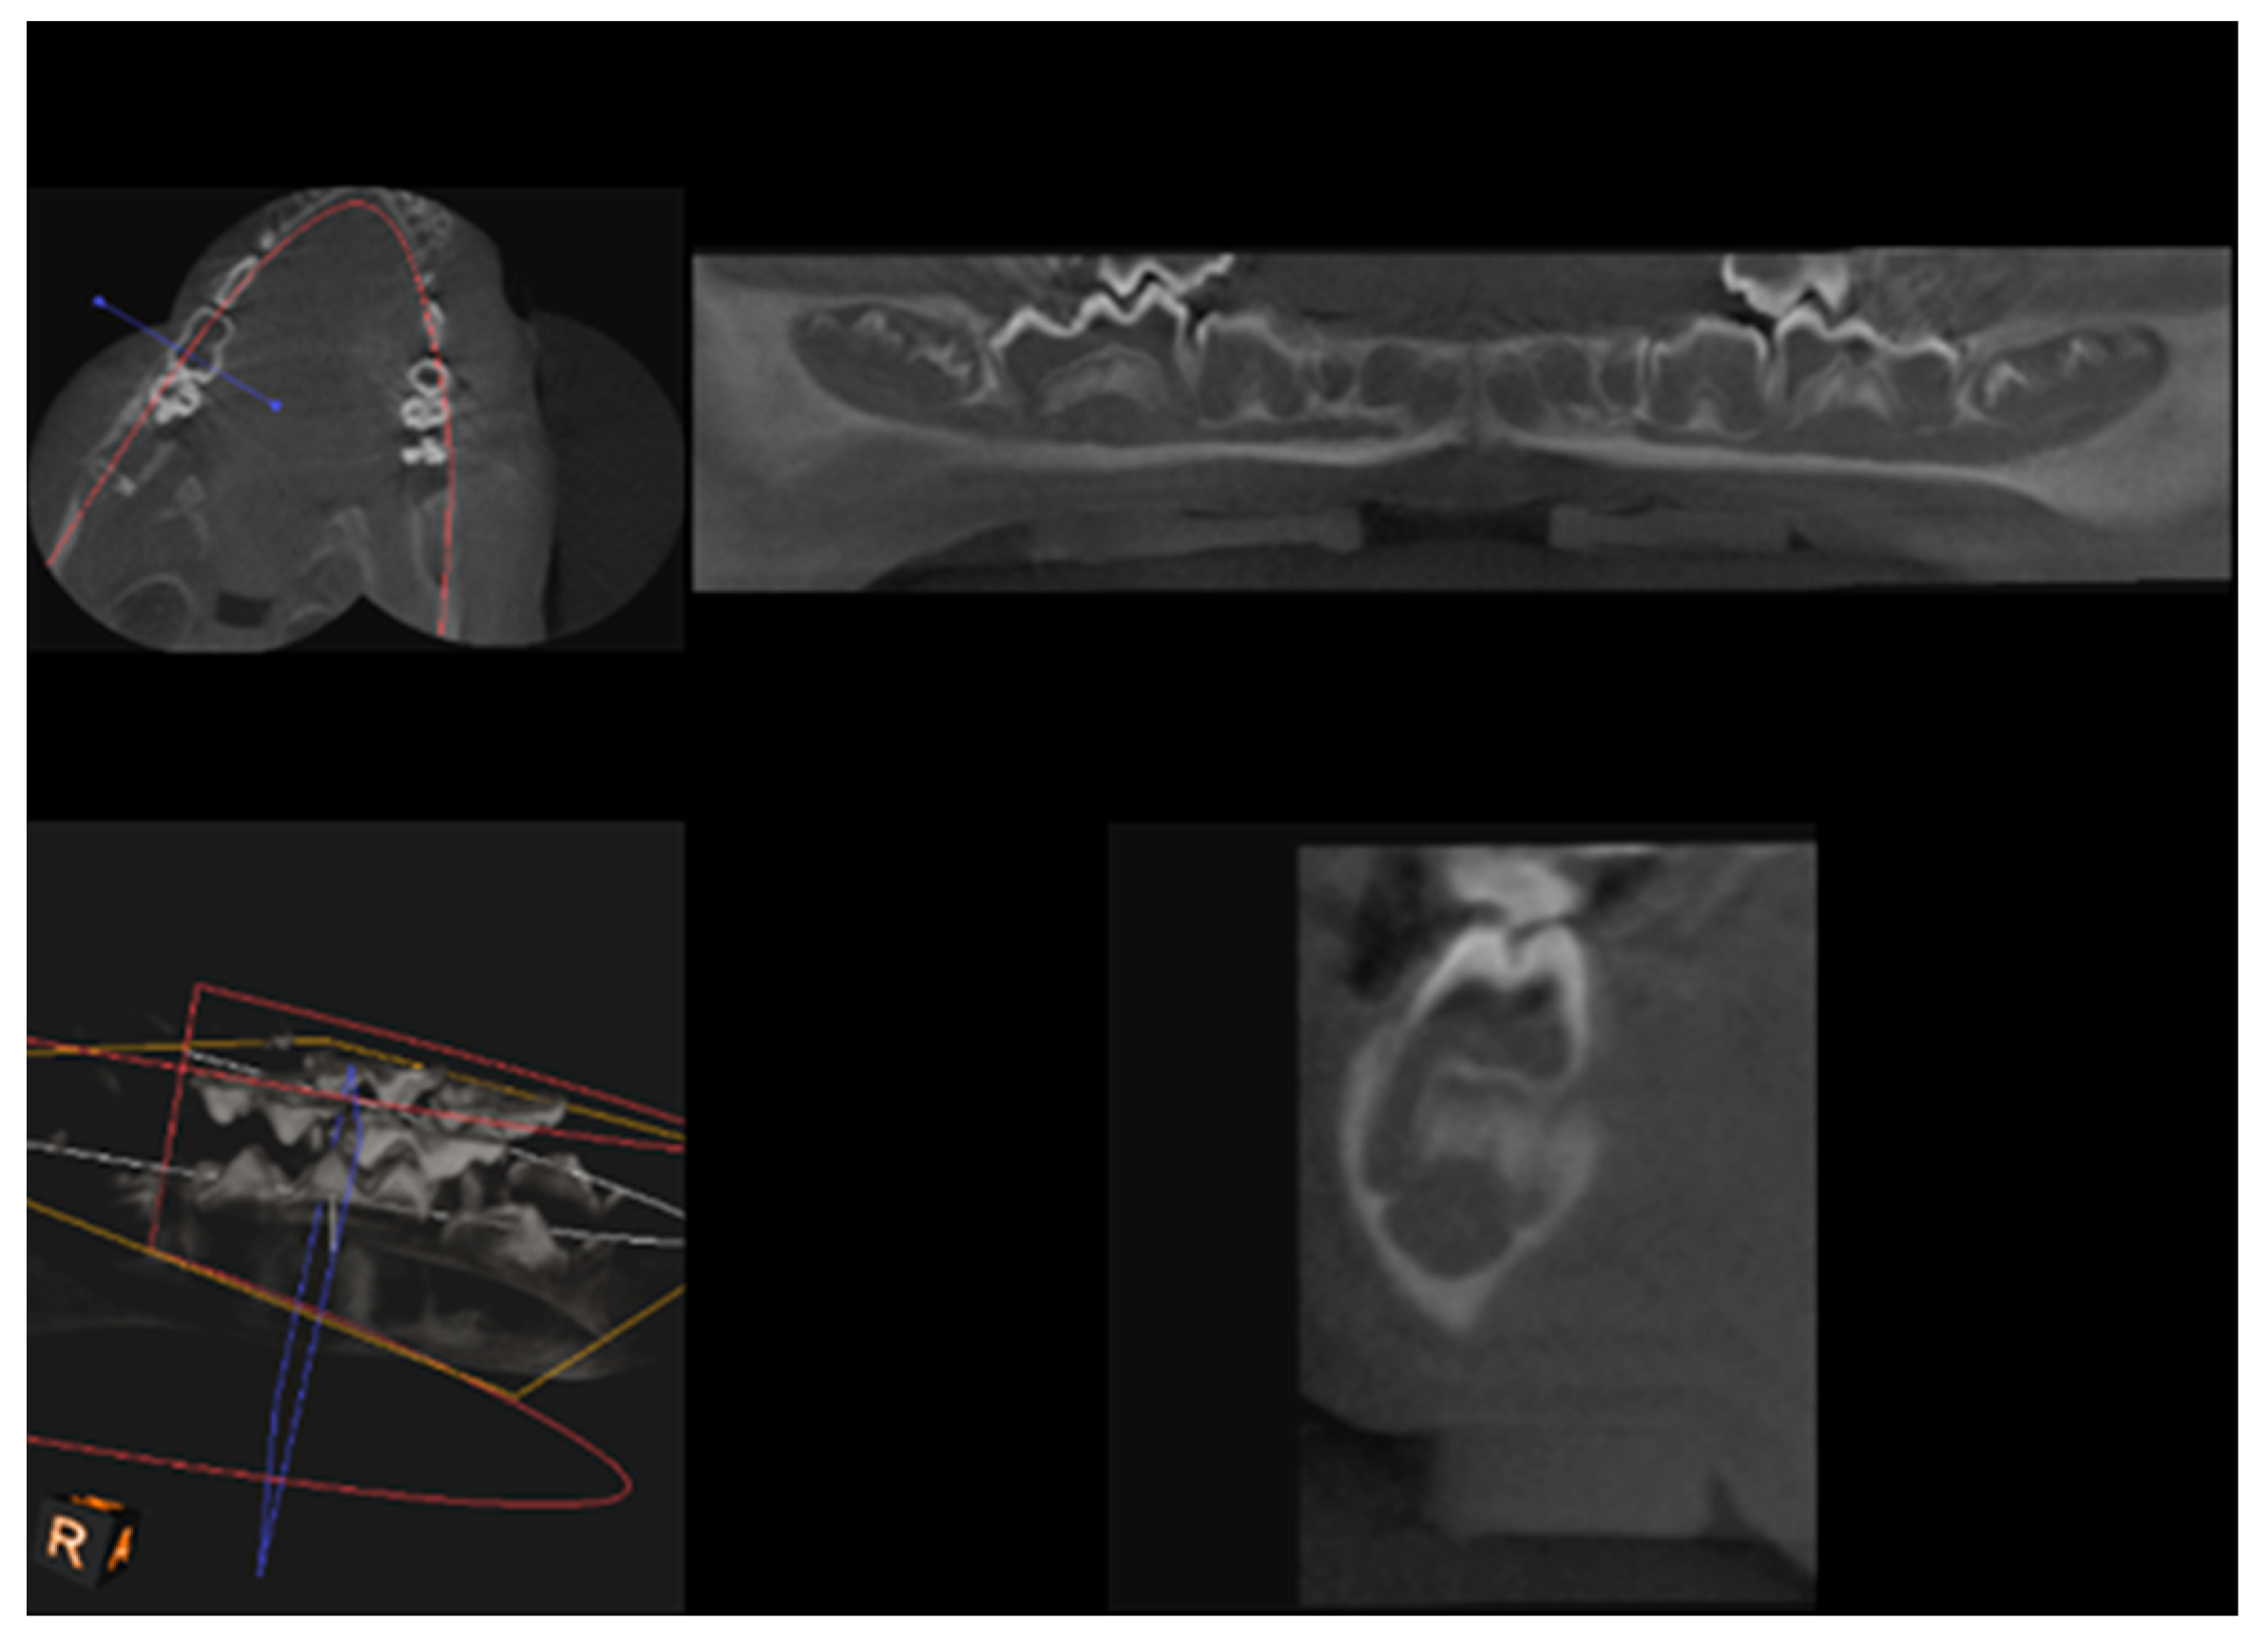

CBCT examination, with a Kodak 3000C 3D system (Kodak Dental Systems, Atlanta, GA, USA), together with Dental Imaging Software ver. 6.12.32 (Kodak Dental Systems, Atlanta, GA, USA), was performed before and immediately after germectomy and then again on the extracted jaws of the piglets after euthanasia with a voxel size of 160 μm, a 0.16 mm space between slices and a field of view of 13 × 10 cm, 90 kV and 4 mA. CT sections were used to assess the width and height of the bone, the thickness of the base plate, the tongue and vestibular side, the dimensions of the marrow cavities, and the height of the mandibular alveolar part. Four measurement planes were determined in the area from the first to the third milky premolars on the dentition side, and then, similarly to the manual measurements, measurement planes were determined for the operated side at the same distance from the line connecting the most distal points of the condylar process and the mandibular angle, in a line parallel to the lower edge of the mandibular shaft. Figure 3 and Figure 4 show an example of a CT scan image of a piglet’s mandible before (Figure 3) and after surgery (Figure 4) and Figure 5 and Figure 6 are diagrams of the external (Figure 5) and internal measurements (Figure 6) of the mandible of the piglets.

Figure 6.

Diagram of internal measurements of the mandible of piglets—left and right sides.